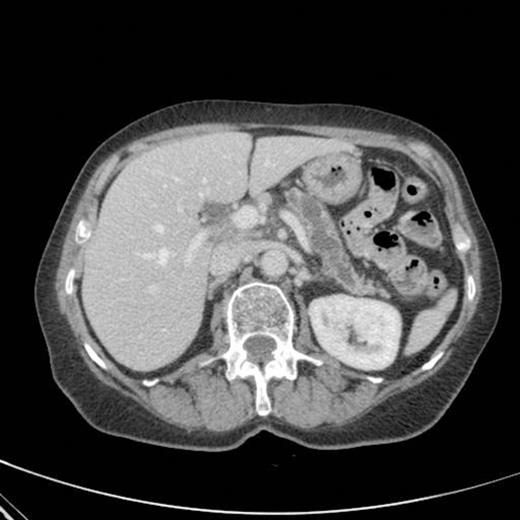

A subsequent CT scan done a year later confirmed the persistence of the gastro pancreatic fistula with polypoid herniation into the stomach and this was thought to represent main duct IPMN with mucinous tumour herniation into stomach (Fig 4). An upper GI endoscopy confirmed the gastric opening of the fistula at 50 cm on the lesser curve with a mucus plug sealing the opening (Fig 5). Biopsies were taken from around the fistulous opening and this was reported as non-specific inflammation. Again, a surgical option was offered that was declined by the patient and hence it was decided to continue with regular follow up and conservative management.